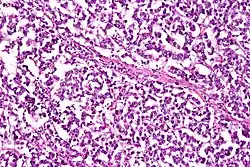

Dysgerminoma

Dysgerminomas are comparable to testicular seminomas and account for approximately 32- 37% of all OGCTs.[1] They are particularly prominent in individuals with dysgenic gonads of 46, XY pure gonadal dysgenesis patients.[1] Based on gross examinations, dysgerminomas are characterized by having a ‘solid, lobulated, tan, flesh-like gross appearance with a smooth surface'.[1] Microscopically, the cellular structure is distinguished by a round-ovoid shape containing ample eosinophilic cytoplasm and an irregularly shaped nuclei.[1] The uniformly positioned cells are separated through the fibrous strands and lymphocytic infiltration is commonly observed.[4]